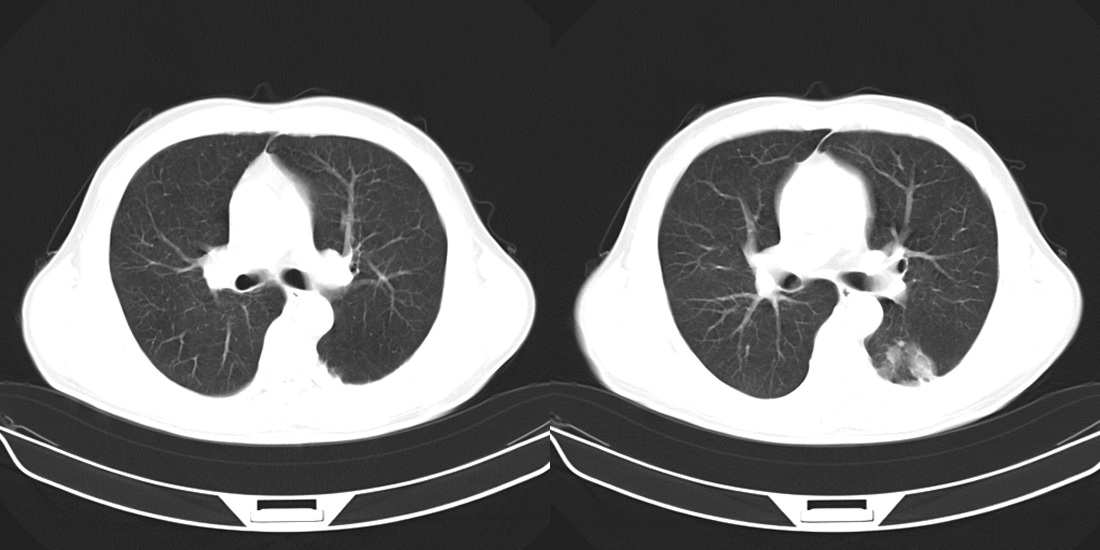

标题: CT10251:男性56岁,结核球? [打印本页]

标题: CT10251:男性56岁,结核球?

56岁男性,低热、消瘦,曾x线诊断肺结核。

两肺结核,左肺结核球。

双肺结核伴左上肺结核球形成

两肺多形性病变,支持肺结核.

两肺多形性病变,且在结核好发部位。支持肺结核.